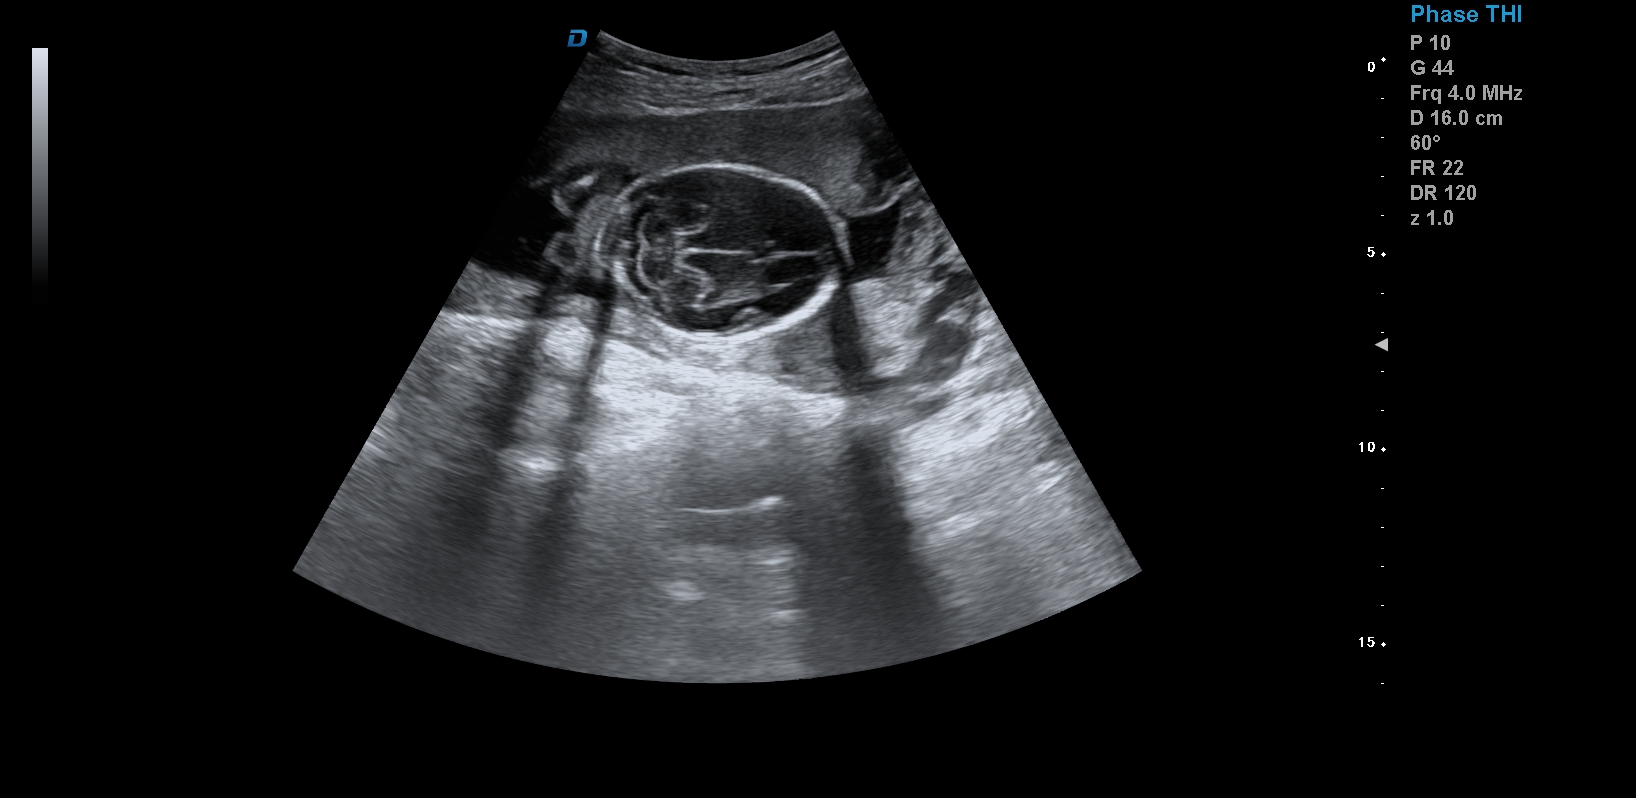

四維彩超,見證生命最初的感動

醫用四維彩超機作用

首先,四維彩超檢查是采用高清晰度的彩超儀對胎兒進行各個心臟器官及組織的一次全面檢查,可以立體顯示胎兒的發育情況,胎兒在子宮內的任何狀態都可以觀察到。對胎兒畸形能夠早診斷,及時地做出相應的措施,以達到優生優育的標準。

四維彩超不但成像清晰,更是在三維的基礎之上附加時間這個矢量。這就在排畸的同時能時刻觀察寶寶在宮內的一舉一動,吃手指、打哈欠、吮吸……寶寶在宮內憨態可掬,讓孕媽媽母愛井噴,幸福不已。這也是孕媽媽們選擇四維的主要原因,試想,誰不想在辛苦懷孕期間提前看一看自己寶寶的模樣呢?

1、四維彩超是目前先進的彩色超聲技術.能直觀立體現實人體器官動靜態三維結構,一定程度上提高臨床診斷的準確性。

2、安全方式:此種超生診斷儀擁有出色人體工程學設計模式,不存在射線、光波和電磁波等方面輻射,對母體胎兒均無任何影響.

3、清晰成像:采用先進的超聲成像技術,擁有高清晰,高分辨率、高精確度優點,能清晰看到包括生殖器、內臟器官在內的胎兒的各個部位發育情況.

四維彩超最佳時間是24-26周。這個時候胎兒結構發育完善,可觀察到大多數的胎兒畸形。胎兒30周左右最好再去做一次四維彩超,因為胎兒結構是一個逐漸發育的過程,畸形沒有發展到一定程度可能不能被檢查到。

四維彩超臨床圖